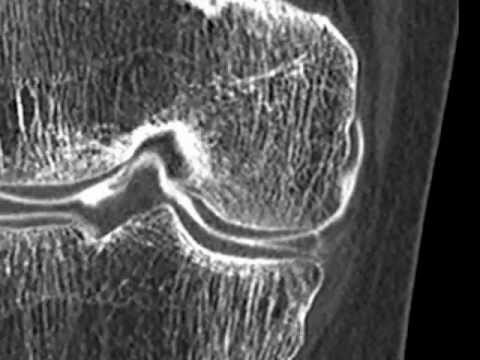

Fissure-Menisque-medial-Arthroscanner-3D :

comment soigner menisque